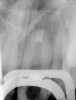

Fig 2. MTA placed in the apical third.

Figure 2

Clinical procedure: If apical bone loss is present (Figure 1) a collagen/gelatin sponge (eg, Gelfoam®, Pfizer Inc., www.pfizer.com) can be placed apically so that the MTA can be delivered to the desired working length. (Any other surgical resorbable sponge would also work, such as OraPlug® [Salvin Dental Specialties, www.salvin.com], Surgifoam® [Midwest Dental, www.mwdental.com], or Surgispon® [Aegis Lifesciences, www.surgispon.com]). This is done by taking a small piece (2 mm x 2 mm) of the resorbable sponge and pushing it down to and through the root apex with an endodontic file. Once this is done, MTA is packed down the canal with a custom-fitted cone. The clinician can use a rubber stopper on the gutta-percha cone to know the exact length of MTA placed in the apical third (Figure 2). Once the apical third is sealed with 3 mm to 5 mm of MTA, the remaining coronal canal space can be back-filled using a warm gutta-percha technique (Figure 3).